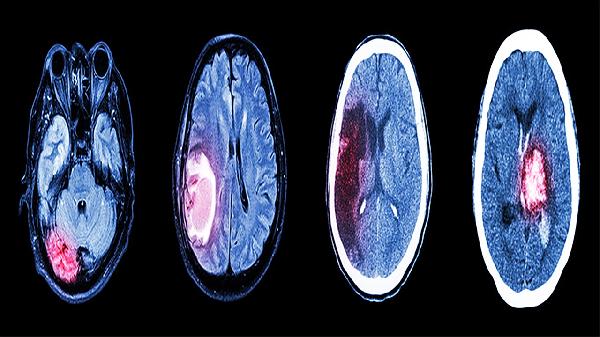

建议保持每日7小时深度睡眠,工作间隙做颈椎米字操。饮食注意补充优质蛋白和B族维生素,避免高脂高糖饮食。若调整生活方式后症状仍持续,或伴随呕吐、肢体麻木等症状,需及时进行脑部CT或经颅多普勒检查排除器质性疾病。高血压患者应定期复查肝肾功能,避免擅自调整药物剂量。